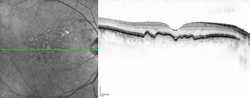

Macular hard drusen in the right eye. 65-year-old diabetic woman.

Drusen in optical coherence tomography.